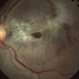

- Macular Pucker

- epiretinal membrane formation

- Pre-op patient for surgery for epiretinal membrane stripping in the left eye.